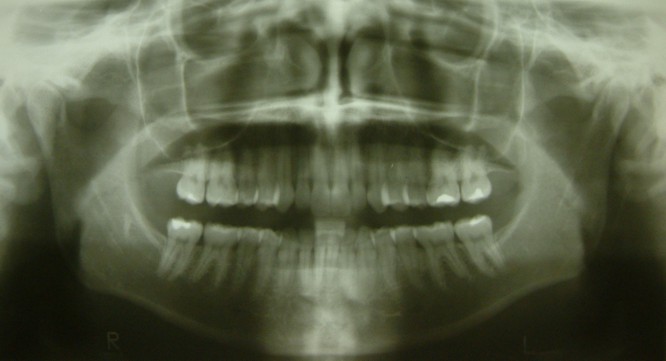

Un’altra fase della diagnosi è rappresentata dalla radiografia panoramica che  fornisce indicazioni sulla presenza, e sullo stato dei denti permanenti, sulla loro direzione di crescita e stadio di sviluppo e chiarisce i rapporti esistenti tra denti decidui e i denti permanenti o alla teleradiografia che  permette lo studio dei rapporti reciproci sia dei denti che delle due arcate dentali e l’analisi di queste ultime con le basi ossee e delle basi ossee con il cranio. Sulla base della teleradiografia si esegue la cefalometria che consente l’esatta diagnosi delle maolocclusioni e lo studio della crescita della faccia. Le fotografie infine consentono al dottore di analizzare lo studio della faccia e del profilo, in modo da armonizzare con l’intervento ortodontico i denti e le ossa mascellari di profilo del singolo paziente.